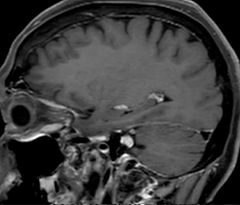

Acute right motor deficit and aphasia

In this patient with acute right motor deficit and aphasia, the b2000 diffusion weighted image is normal. The SWIp image demonstrates more prominent veins in the right hemisphere, which could reflect increased deoxyhemoglobin contents. Fast ASL shows low CBF regions in the left frontal lobe. A follow-up ASL after one hour demonstrates high CBF values in the same area. The final diagnosis was migraine with aura.